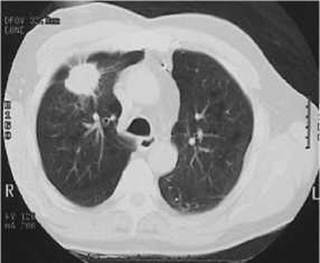

Х-променеве та КТ-дослідження виявляє периферійний рак у вигляді вузла або маси діаметром 2-4 см і більше, як правило, у верхніх частках легень, частіше справа. Важливими ознаками периферійного раку легені є: 1) неправильна куляста форма, що виявляється на КТ та рентгенологічному багатоосьовому дослідженні хворого (мал. 122, 123); 2) неоднорідна структура тіні пухлини, яка складається з окремих вузлів, що визначається на рентгенограмах, звичайних і комп’ютерних томограмах; 3) нерівні, горбисті, на окремих ділянках нечіткі, змазані контури тіні; 4) незмінена легенева тканина навколо тіні ракового вузла; 5) наявність в окремих випадках «доріжки» до кореня легені, зумовленої дрібними метастатичними висипаннями, або проростанням пухлини вздовж лімфатичних судин (раковий лімфангоїт); 6) стовщення плеври, спайки, зрощення, або плевральні випоти, які спостерігаються при близькому розміщенні пухлини до плеври; 7) порожнина неправильної форми з нерівними краями, без горизонтального рівня, яка з’ являється при розпаді пухлини і краще виявляється на комп’ютерній або лінійній томограмі (мал. 124, 125).

Мал. 123. Периферійний рак правої легені на комп’ютерній томограмі.